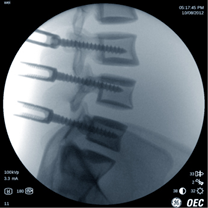

Lombare con AutoTrak